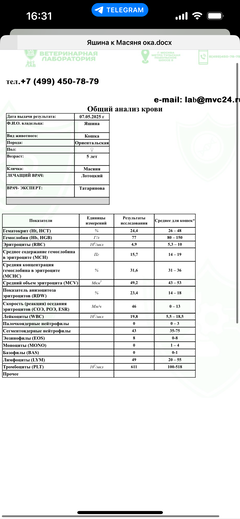

Была куплена в питомнике взрослой. У Масяни начались проблемы с кишечником и она стала подтекать и все пачкать. Надо отдать должное хозяевам - ее обследовали вдоль и поперек - как говорили местные врачи, сдавали много анализов но диагноза так и не поставили.

Ярко выраженная болезненность в области крестца, на обезболе полегче. По результатам приема невролога проведена миелография - множественная компрессия, возможно опухоль, возможно грыжа, нужно удалять...